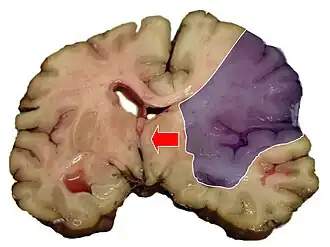

Een cerebrovasculair accident of cerebrovasculaire aandoening (CVA), in het Nederlands beroerte, attaque en apoplexie, is een acute medische aandoening waarbij er een plotselinge verstoring van de doorbloeding van de hersenen plaatsvindt. Er zijn twee hoofdtypen CVA: herseninfarct en hersenbloeding. Bij het herseninfarct wordt een bloedvat afgesloten en stopt de doorbloeding. Bij een hersenbloeding gaat een bloedvat kapot. Het uiteindelijke resultaat van beide typen is dat de hersenen niet goed meer werken.[1]

Indeling

CVA's kunnen worden ingedeeld in twee categorieën: herseninfarct en hersenbloeding.[6] Een herseninfarct ontstaat als de bloedtoevoer naar de hersenen wordt onderbroken. Een hersenbloeding kan ontstaan doordat een bloedvat scheurt of door een misvorming. Zo'n 87 procent van de beroertes zijn herseninfarcten en de rest zijn hersenbloedingen. Bij een herseninfarct kunnen er in het aangedane gebied bloedingen ontstaan. Dit wordt "hemorragische transformatie" genoemd. Het is niet bekend hoeveel hersenbloedingen beginnen als herseninfarct.[2]

Herseninfarcten

Bij een herseninfarct neemt de bloedtoevoer naar een deel van de hersenen af. Hierdoor raken de hersenfuncties in het getroffen gebied verstoord. Er zijn vier redenen waarom een ischemische beroerte kan plaatsvinden:

Herseninfarcten ontstaan door een plotseling verminderde bloedtoevoer naar een gedeelte van de hersenen. Dit kan op verschillende manieren, onder andere: